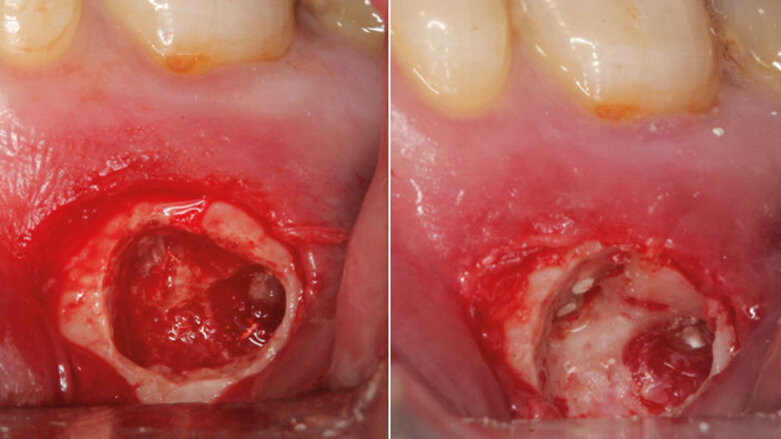

The aim of the current investigation was to review techniques and materials available to achieve bleeding control during periapical surgery. An adequate bleeding control is crucial, since it improves vision in the surgical site, minimizes surgical time, enhances the root-end resection and filling, and reduces surgical blood loss, postsurgical hemorrhage and postsurgical swelling.

Results: The hemostatic agents that have been proposed in the literature have characteristics that make them very different from each other, such as the mechanism of action, commercial presentation, hemostatic efficacy and systemic effects.

Conclusion: The hemostatic agents that have obtained the best results are ferric sulfate, calcium sulfate, aluminum chloride and epinephrine. Nevertheless, there is no consensus in the literature on which is the ideal hemostatic agent.